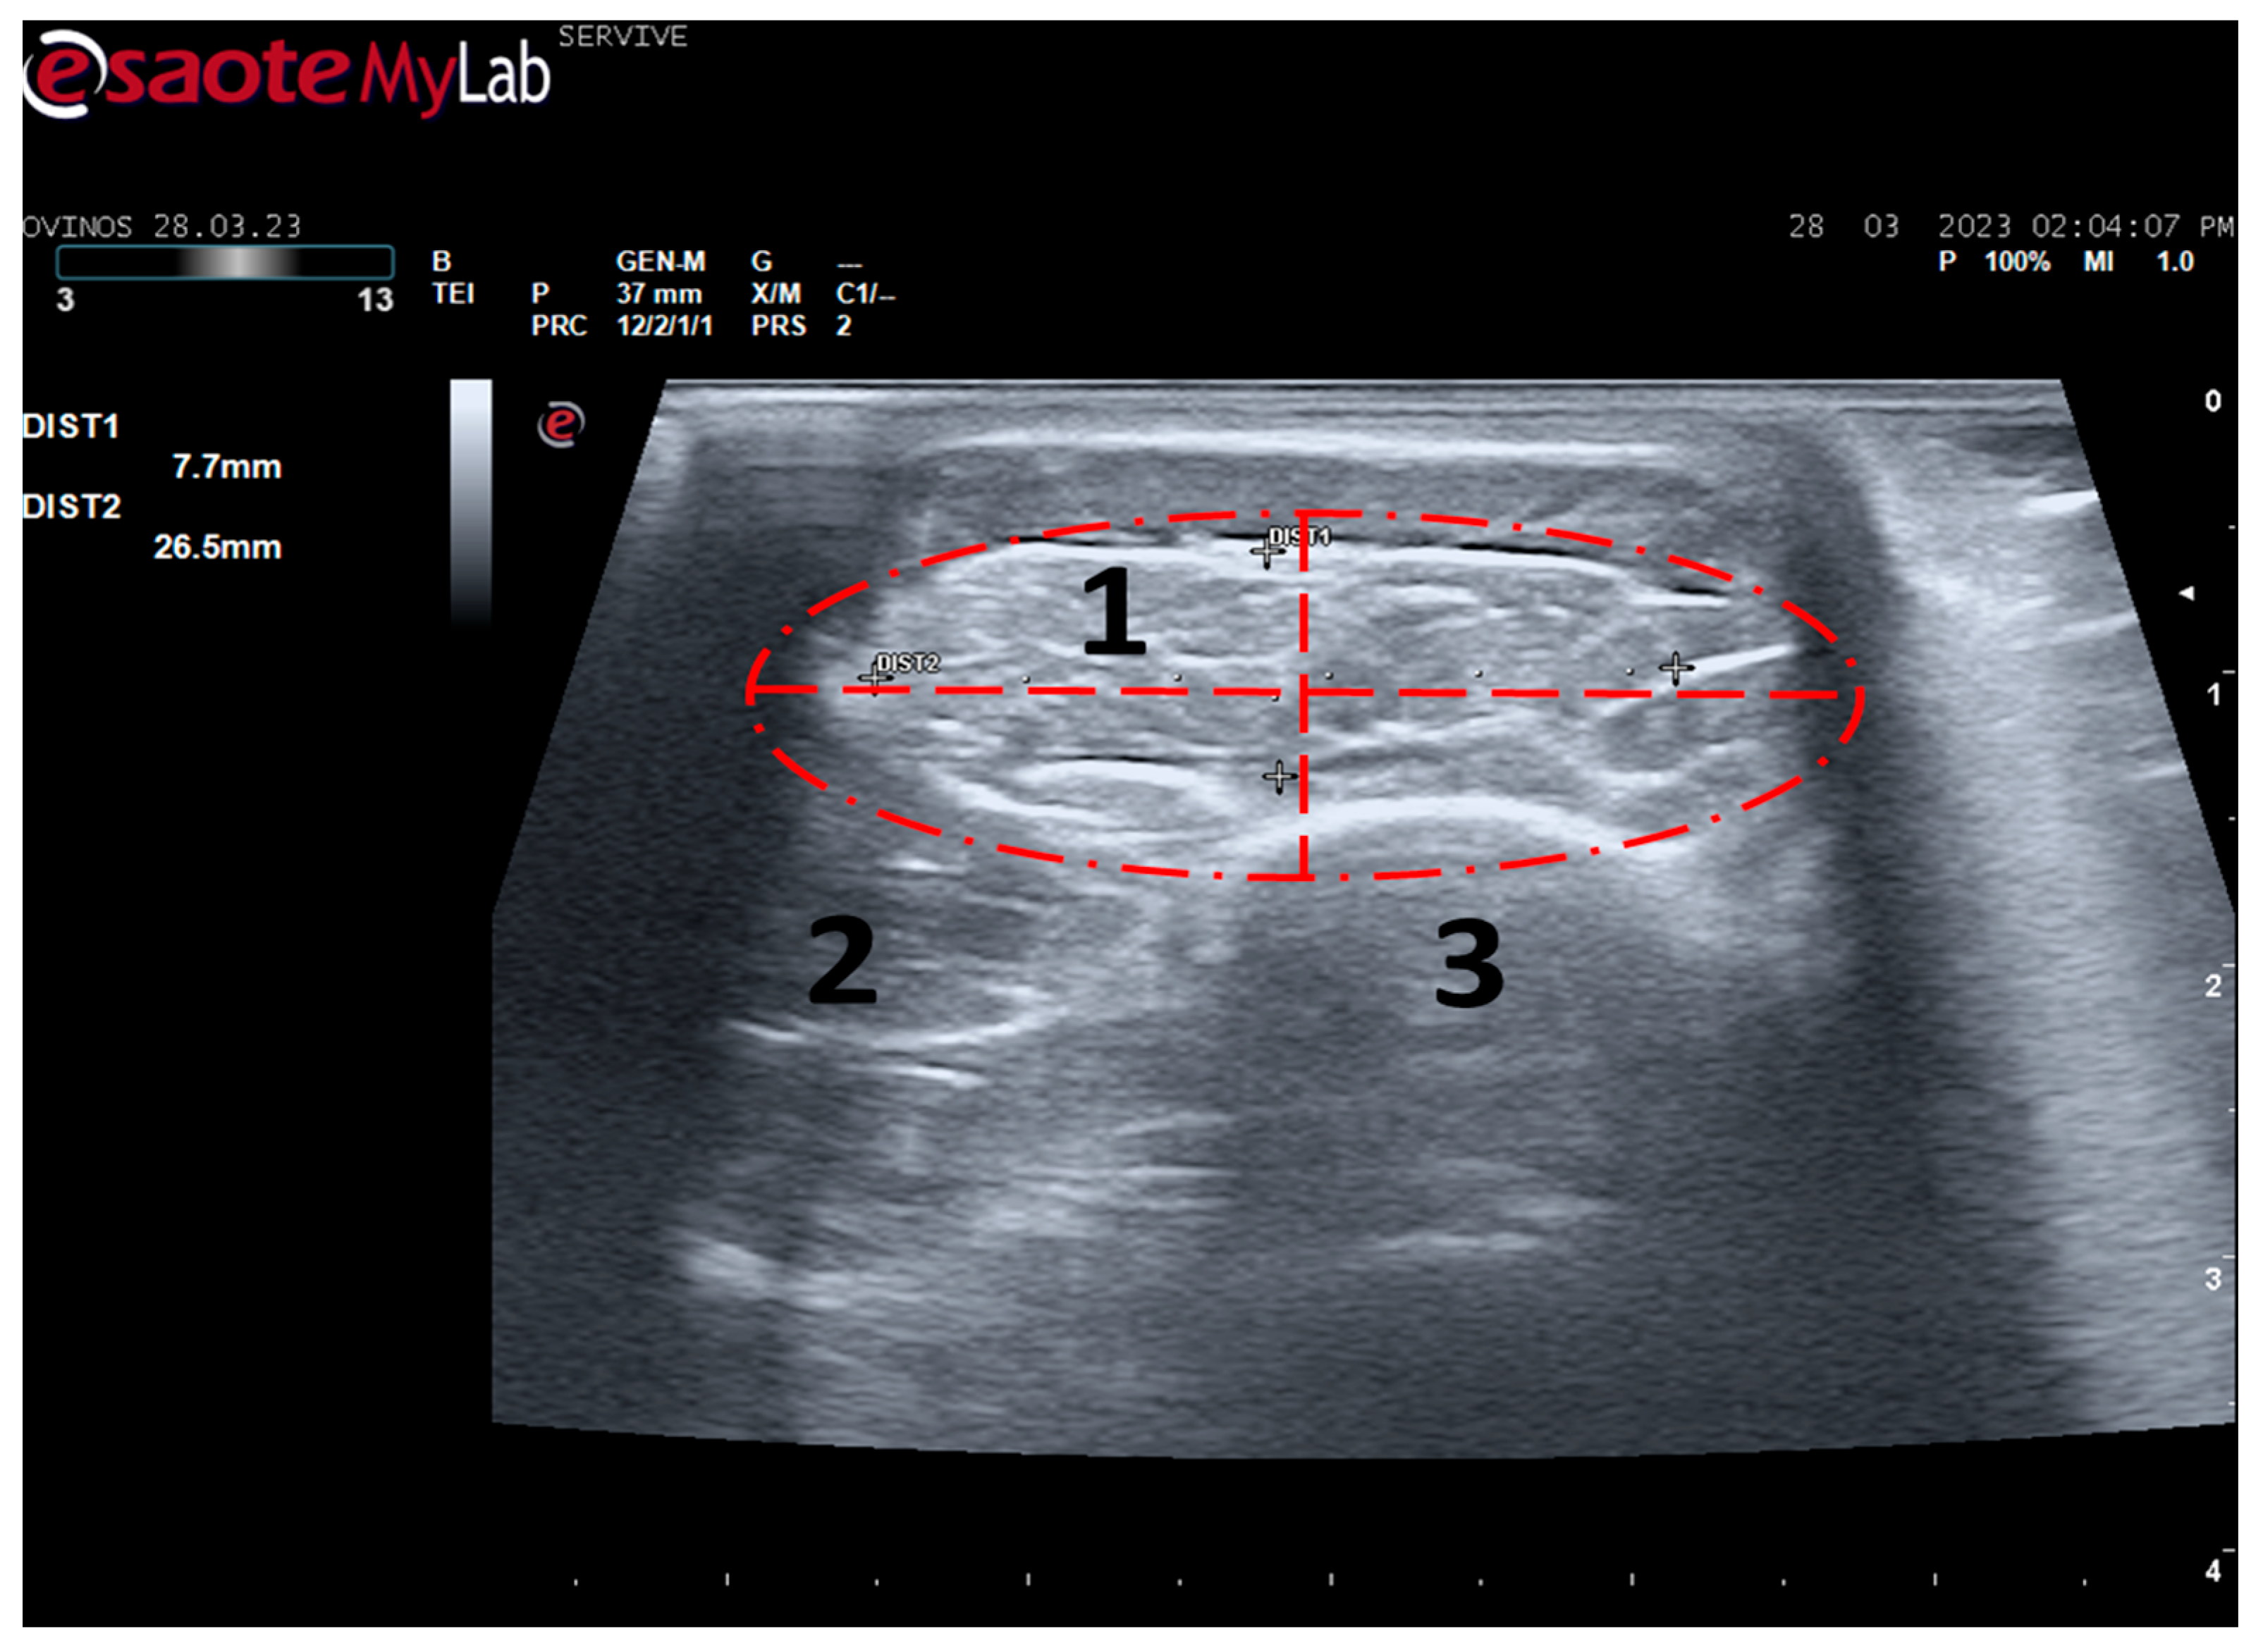

Tibialis cranialis muscle width and thickness were determined in triplicate at three different levels: close to its origin, in the middle of its muscle belly, and close to its insertion. The ultrasound appearance of the muscle is speckled due to the reflection of the perimysial connective tissue, which appears moderately echogenic and allows the fascial architecture of the muscle to be seen. The limits of the muscle are clearly visible since the epimysium that covers it is a very reflective structure (Figure 7). The muscle appears as the first muscle mass arising laterally to the crest of the tibia, occupying a craniolateral position in the leg, cranially to the tibia. The thickness and width values measured close to its origin, in the middle of its muscle belly, and close to its insertion can be found in Table 2. As expected, the dimensions of the muscle are greatest in the middle of the belly of the muscle, being smallest close to the insertion site on the tarsus and metatarsus, and presenting intermediate values at their origin in the lateral condyle of the tibia, lateral edge of the tibial tuberosity, and small surface on the lateral surface of the tibia.

Figure 7.

Ultrasound image of the left cranial tibial muscle taken close to its origin, bounded by the red dashed circle. (1) Tibialis cranialis muscle; (2) extensor digitorum longus muscle; (3) tibia. DIST1 (vertical red dashed line) and DIST2 (horizontal red dashed line) represent the thickness and width of the muscle, respectively.

Among the muscles innervated by the common peroneal nerve is the cranial tibial muscle, a muscle with functions of flexion of the tarsus, extension of the digits, and flexion of the stifle. Due to its anatomical position, this muscle is easily identifiable in a craniolateral position regarding the tibia and can be accessed both by palpation and ultrasound. When a common peroneal nerve injury occurs, the tibialis cranialis muscle is among those that may suffer atrophy by denervation, and its collection for histomorphometry analysis is common to compare the level of histological reorganization of the muscle with the quality of nerve regeneration [5]. In this work, the cranialis tibialis muscle of sheep was also evaluated for characterization, description of its ultrasound image, and determination of normal dimensions in animals not subject to injury. The muscle was easily identified by ultrasound, extending from the condyles of the tibia to the tarsus/metatarsus along the lateral aspect of the leg. The muscle appears delimited by the hyperechogenic epimysium that differentiates it from other extensor muscles in the vicinity and also from the tibia more deeply. The muscle mass is speckled due to the presence of echogenic connective tissue from the perimysium between the nerve fascicles. The two main dimensions of muscle, width and thickness, were measured in three different positions to establish normal values for healthy muscles. These data will be important in future work to compare muscle characteristics in healthy animals with those subject to denervation atrophy after injury of the common peroneal nerve. In this situation, the muscle will tend to lose muscle mass, appearing with reduced dimensions, and may also appear hyperechogenic due to phenomena of fibrosis, inflammation, and fatty infiltration [8,29].